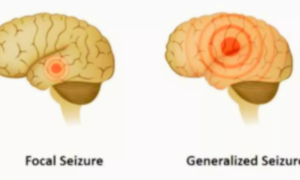

Early Drug Resistance in Focal Epilepsy Linked to Seizure Frequency and Psychiatric History: JAMA

Australia: A new study published in JAMA Neurology highlights…